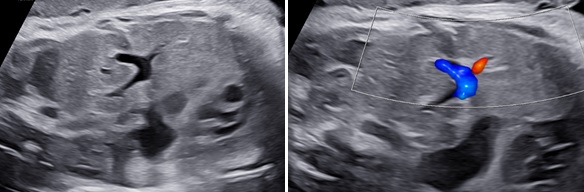

Thoát vị hoành phải nếu chỉ đơn thuần gan lên có thể khó nhận diện vì phản âm của gan tương tự phổi trên siêu siêu âm thang xám. Hình ảnh đường mật, túi mật là đặc trưng giúp nhận diện gan. Doppler màu có gía trị vì giúp nhận diện các tĩnh mạch gan. Dấu hiệu gián tiếp có thể thấy là hình ảnh trục tim bị lệch.

5.2 Vị trí gan

Thoát vị gan có thể xảy ra cả CDH bên trái và bên phải.Trong trường hợp thoát vị bên phải, gan gần như luôn luôn thoát vị do vị trí khiếm khuyết cơ hoành ở bên phải. Mức độ gan thoát vị có ý nghĩa tiên lượng tỷ lệ sống còn sau sinh của CDH bên phải không vẫn chưa rõ vì tần suất bệnh hiếm và chưa có nhiều nghiên cứu. Theo Hedrick [8], tỷ lệ sống còn không có sự khác biệt ở nhóm có TLV > 25 hay ≤ 25 (38% và 35%).

*Điểm thực hành

Thực hiện mặt cắt dọc cơ thể thai nhi qua ngực và bụng thai cho thấy phần gan thoát vị vào lồng ngực với các cấu trúc mạch máu và đường mật bên trong. Nhu mô gan cũng có thể được xác định trong mặt phẳng ngang lồng ngực như một khối đồng nhất với cấu trúc mạch máu hình ống tương ứng với các nhánh của tĩnh mạch cửa.

Các dấu hiệu có thể giúp xác định cấu trúc thoát vị là gan:

1. Phổ Doppler các mạch máu gan theo mặt phẳng dọc hoặc mặt phẳng trán: hình ảnh các mạch máu này hướng lên trên bờ cơ hoành được chẩn đoán là thoát vị gan

2. Hình ảnh ống tĩnh mạch và túi mật: sự hiện diện của bất kỳ các cấu trúc này trong lồng ngực được chẩn đoán là thoát vị gan.

3. Hình ảnh tĩnh mạch rốn đoạn chia nhánh ra tĩnh mạch cửa trái trên Doppler màu trong mặt cắt ngang tại vị trí chu vi bụng cong về phía bên trái gợi ý thoát vị gan

Hình 7. A, Mặt cắt đứng dọc bụng thai nhi và lồng ngực thể hiện thoát vị gan trên thang xám và Doppler cho thấy ảnh gan thoát vị với các mạch máu gan bên trong